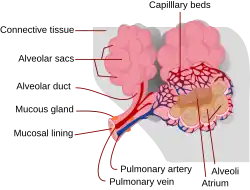

A contusão ou a laceração pulmonar são lesões do tecido pulmonar. A laceração pulmonar, na qual o tecido é cortado ou rompido, se diferencia da contusão pulmonar, uma vez que ocorre desarranjo da arquitetura macroscópica do pulmão,[1] enquanto na contusão não ocorre.[2] Quando as lacerações são preenchidas com sangue, o resultado é um hematoma pulmonar, uma coleção de sangue dentro do tecido pulmonar.[3] A contusão envolve hemorragia no interior dos alvéolos pulmonares (minúsculos sacos preenchidos com ar responsáveis pela absorção do oxigênio), mas um hematoma discreto, não entremeado ao tecido pulmonar.[4] O colapso pulmonar pode ocorrer quando sangue (hemotórax) ou ar (pneumotórax) se acumulam na cavidade pleural (espaço externo ao pulmão). Essas condições não envolvem necessariamente dano ao tecido pulmonar, mas podem estar associadas a ele. Lesões da parede torácica também ocorrem, mas podem estar associadas a lesões pulmonares. Os danos à parede torácica incluem fratura de costelas e tórax instável, no qual múltiplas fraturas de costela fazem um segmento da caixa torácica se separar do resto da parede torácica, movendo-se independentemente.